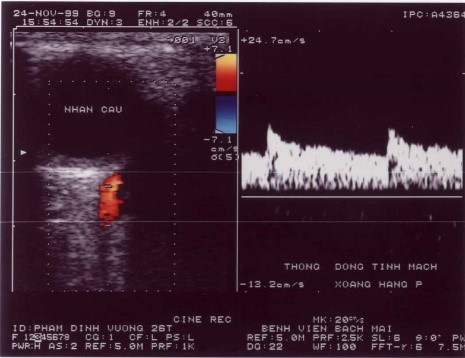

Trung tâm Điện quang từng tiếp nhận người bệnh Nguyễn Văn Đ *. Bệnh nhân sau khi bị tai nạn khoảng vài tháng, xuất hiện lồi mắt, đỏ mắt tăng dần, có thể lác, giảm thị lực, nghe thấy có tiếng thổi hay tiếng ù vùng tai hay vùng mắt tuỳ theo mức độ của luồng thông. Khám thấy lồi và đỏ mắt, nghe có tiếng thổi vùng mắt hoặc thái dương. Trên Siêu âm Doppler thấy tăng tốc độ dòng chảy động mạch cảnh trong bên tổn thương và giảm sức cản, thấy tĩnh mạch mắt giãn, đảo chiều dòng chảy và động mạch hoá.

Nút thông động mạch cảnh xoang hang: a- Hình lồi đỏ mắt trái sau chấn thương. b- Hình CLVT thấy lồi mắt trái. c- Hình Siêu âm Doppler thấy giãn đảo chiều dòng chảy tĩnh mạch mắt. d- Hình thông trực tiếp động mạch cảnh xoang hang, luồng thông lưu lượng trung bình. e- Sau nút bằng 3 bóng, tắc hoàn toàn luồng thông. f- Hình kiểm tra sau nút luồng thông, mắt trái xẹp hết lồi.